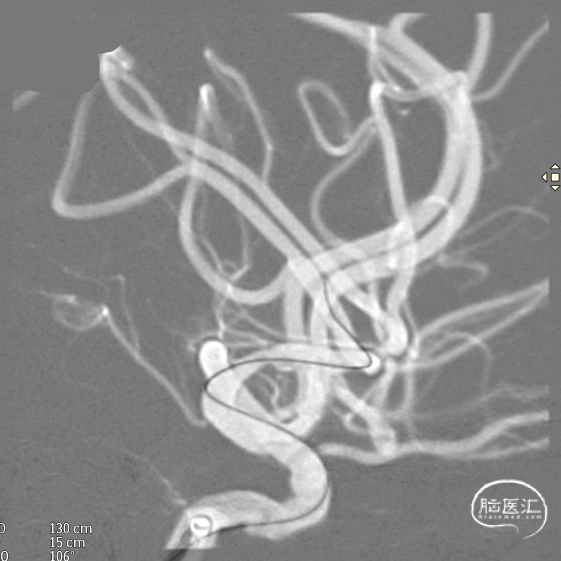

微导管到位:Synchro微导丝引领支架微导管通过病变血管进入大脑中动脉M2段。

支架到位,原位释放,前段打开。

造影确认支架远端打开充分,贴壁良好,继续推送支架。

支架全部释放,调整张力,微导管通过支架,回收输送导丝。

支架内使用成襻微导丝进行按摩,使支架充分贴壁。